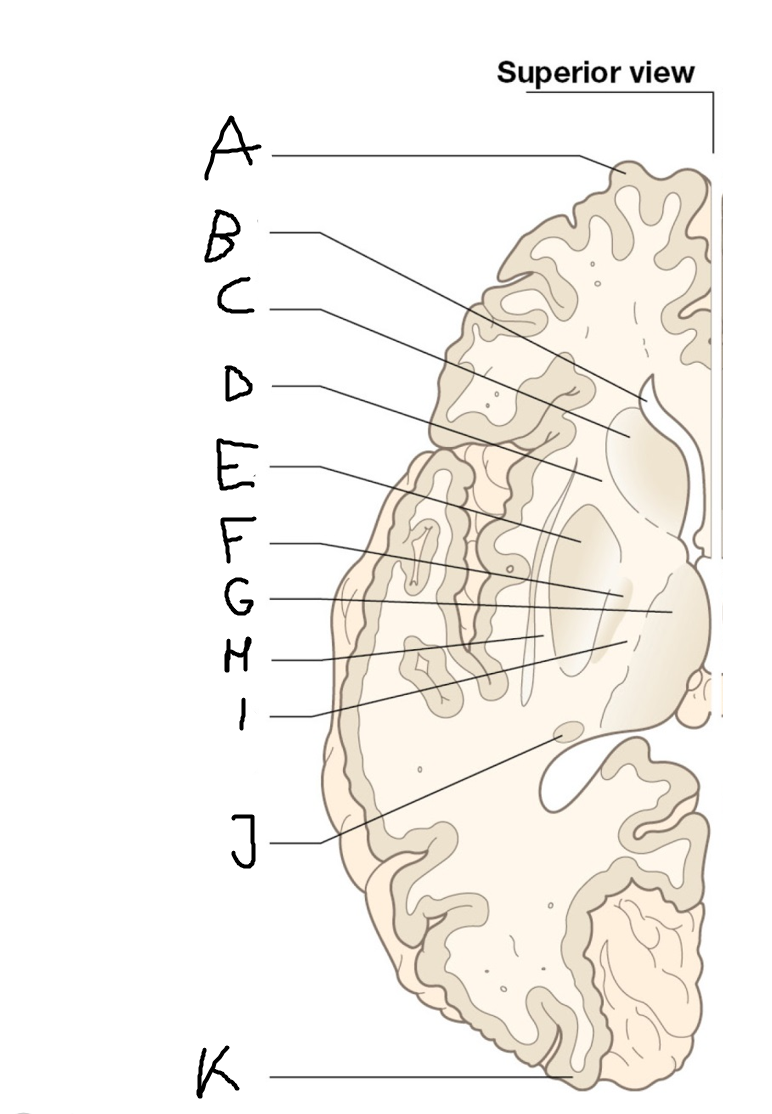

internal capsule (posterior limb)

B

anterior horn of lateral ventricle

C

head of caudate nucleus

D

internal capsule (anterior limb)

E

putamen

F

globus pallidus

G

Thalamus

H

External capsule

I

internal capsule (posterior limb)

J

tail of caudate nucleus